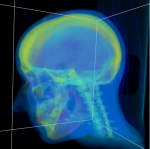

Screenshots

|

|

|

| YaDiV Hauptfenster | Region of Interest | Segmentierung |

|

|

|

| 2D Segmentvisualierung | 3D Segmentvisualierung | Marching Cube |

|

|

|

| Pseudo-Color Darstellung | Settings Browser | DICOM File Info Window |